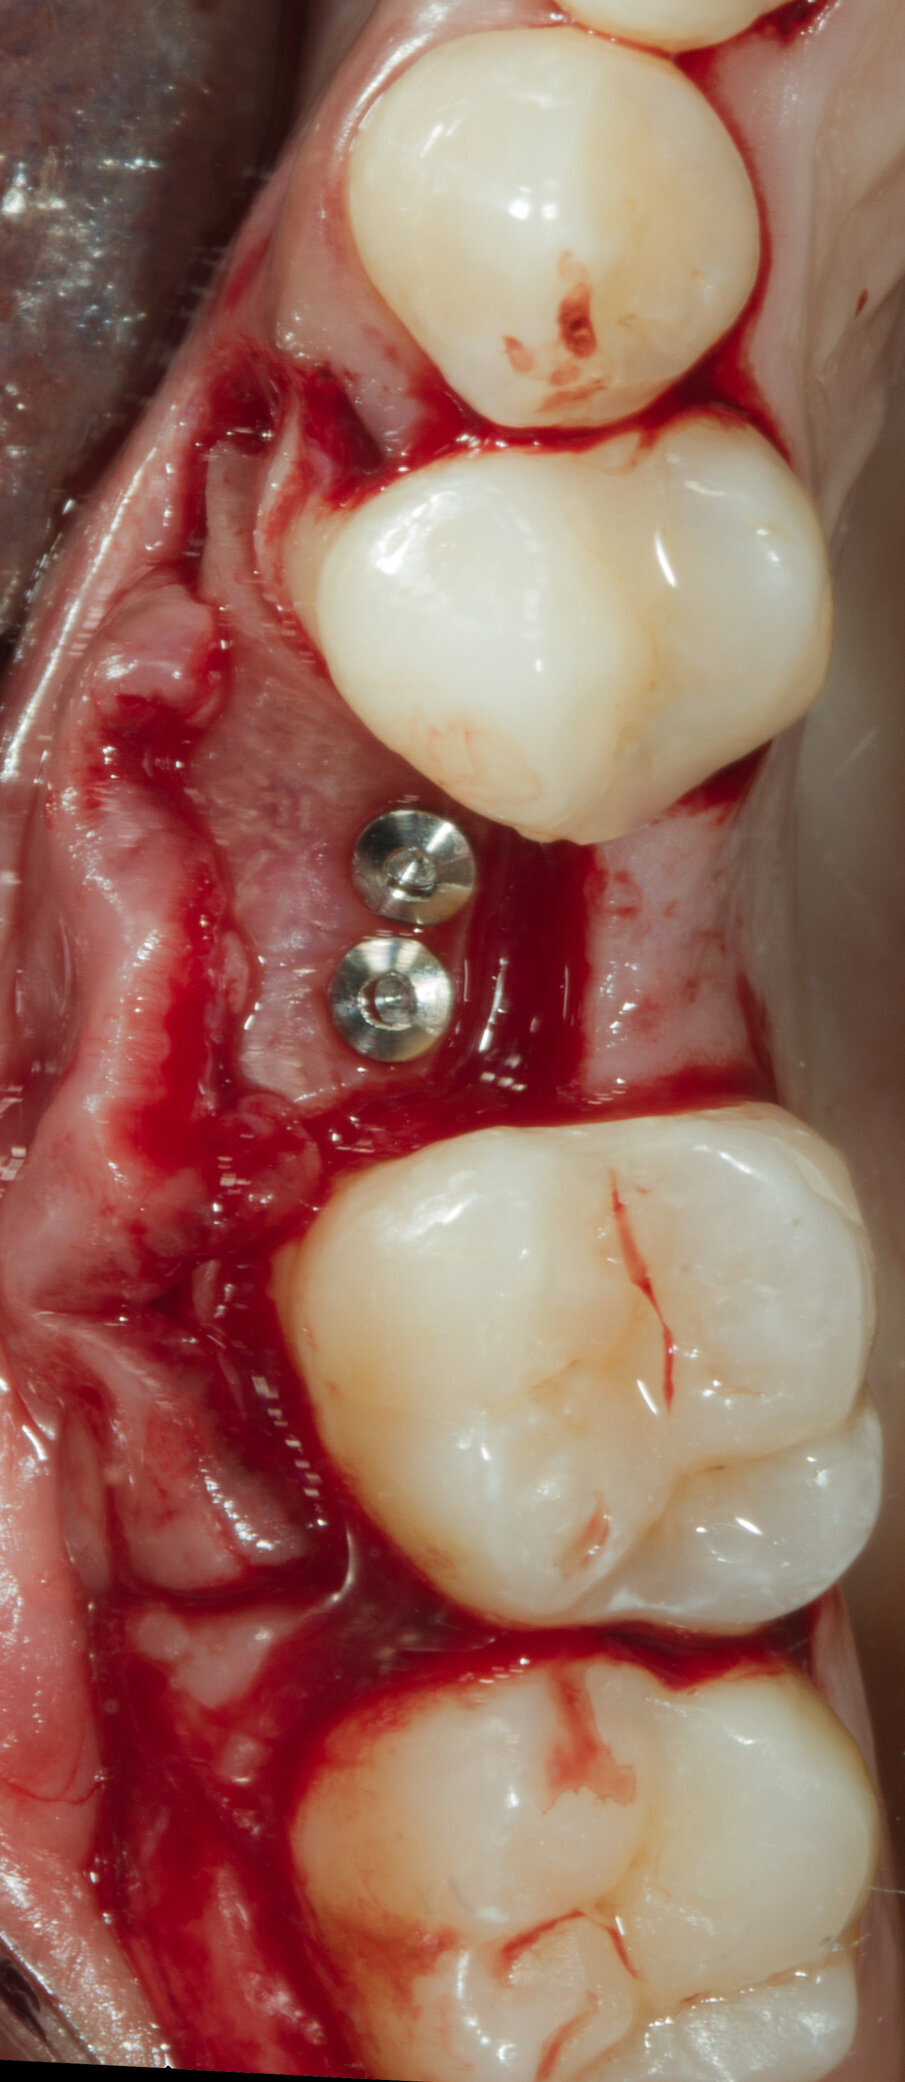

Fig. 12 - Fissazione della Lamina con 2 viti da osteosintesi.

Dopo aver passivizzato il lembo si esegue una sutura a materassaio orizzontale e punto staccato centrale sulla parte crestale e suture semplici sulle incisioni di scarico (Figg. 13, 14). Dopo 10 mesi di guarigione si può procedere all’intervento di posizionamento implantare (Figg. 15-17). Sia dalle fotografie a lembo aperto (Figg. 18, 19) e da quelle di confronto tra la situazione alla baseline e dopo rigenerazione della cresta ossea (Figg. 20, 21) si può valutare come si sia ricostituito un osso ben corticalizzato, vascolarizzato, che ha riempito tutto il difetto osseo preesistente.